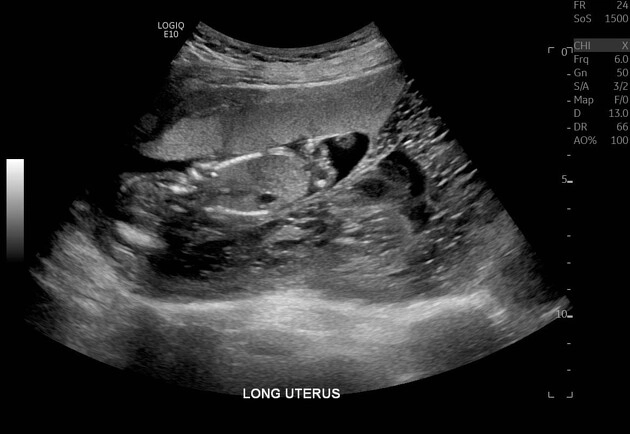

Thai trứng toàn phần (Complete hydatidiform mole)